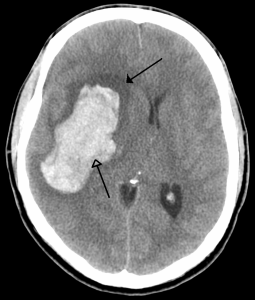

A second study, published simultaneously in Lancet Global Health, takes a closer look at the different subtypes of stroke, finding that haemorrhagic stroke causes more disability and death than ischaemic stroke, despite being less common.